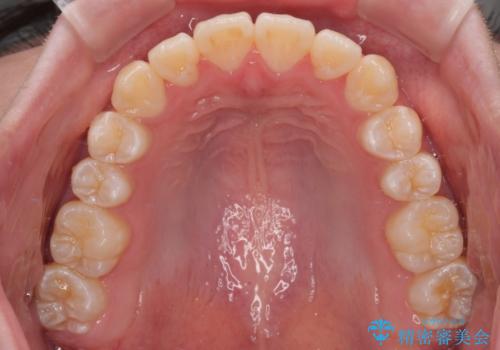

患者様の協力もあり、およそ1年間で治療を完了。スムーズな歯の移動を実現しました。

上下の正中(真ん中のライン)もずれることなく、バランスの取れた美しい歯並びに。笑顔に自信を持てる仕上がりとなりました。

「もっと時間がかかると思っていましたが、あっという間でした。装置も思ったより気にならず、前歯がきれいに並んでとても満足しています。」とうれしいお言葉をいただきました。